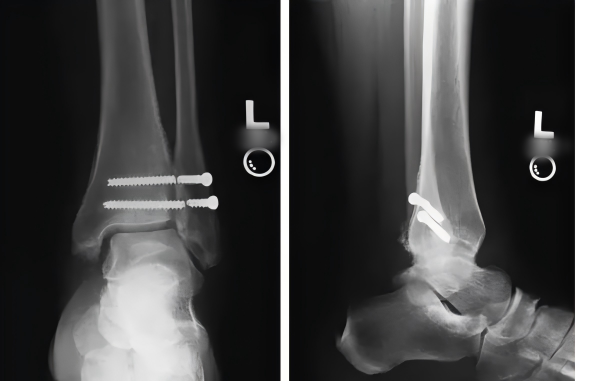

傳統(tǒng)手術(shù)金屬螺釘固定存在風(fēng)險:

不符合踝關(guān)節(jié)下脛腓聯(lián)合生理微動

完全負重前需局麻取出

非取出易產(chǎn)生:螺釘松動、斷裂,螺釘周圍骨質(zhì)吸收和溶解

完全負重推遲導(dǎo)致的股四頭肌等肌肉萎縮